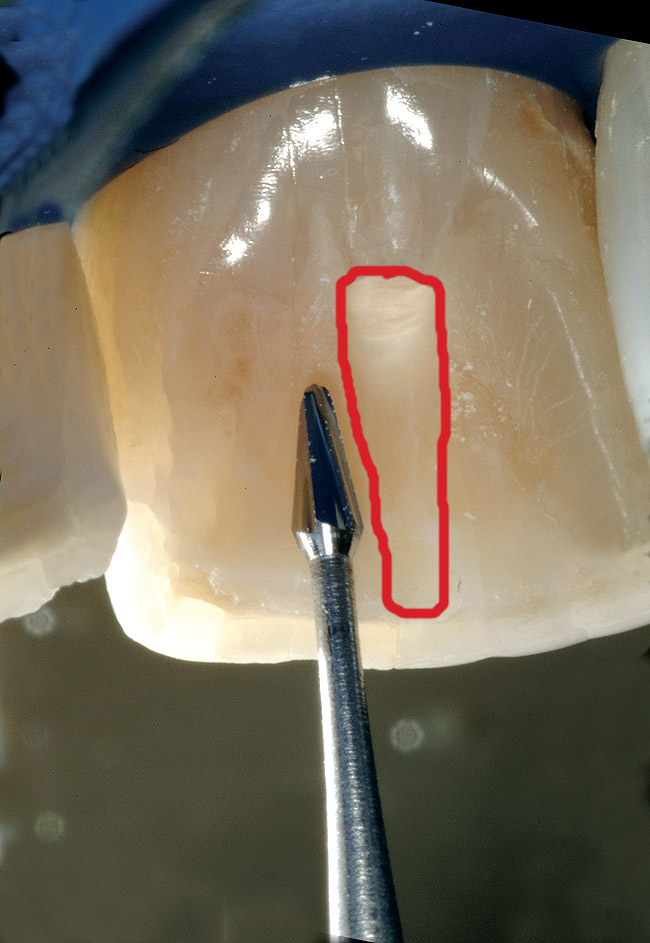

The first step in the access for the calcified tooth is the establishment of the palatal–incisal notch ( Figure 15 and Figure 16). Once the area where the original pulp chamber was located has been accessed, it is advisable to take an orientation verification radiograph or multiple angled radiographs ( Figure 17). The palatal–incisal notch works in concert with the narrow shaft of the bur to perform important tasks. Similar to a surgical stint for implant drilling, the notch first stabilizes and directs the head of the bur by cradling the shaft. Secondly, it allows a more appropriate angulation—toward the incisal—of the back of the bur. Anatomy lessons have taught clinicians that the root and the crown of incisors are not parallel.

The resultant cavosurface outline is quite long and fairly narrow for the calcified tooth, and creates better potential for accuracy ( Figure 18 and Figure 19). A final view of the access in Figure 20 shows the orientation of the palatal–incisal notch and the dentinal map, which is encountered as early as possible. The radiographic sequence ( Figure 21, Figure 22, Figure 23 and Figure 24) teaches a new concept in accessing calcified canals, that of radiographs taken using the pointing quality of a conical bur to assess direction and position of the access cavity. Corrective steps can then be taken to avoid gouging or perforation. In the past, only endodontic files have been used as metallic (radiopaque) radiographic markers. The snug fit of a conical bur as opposed to the loose fit of a round bur facilitates the use of the bur in taking "bur instrument films."